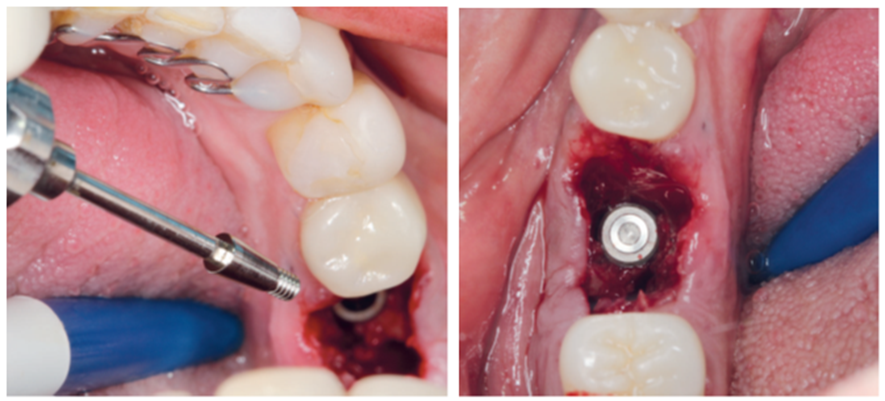

Para a regeneração óssea guiada, o substituto ósseo natural composto por hidroxiapatita bovina e colágeno do tipo I (Extra Graft XG-13) foi introduzido ao redor do implante para preenchimento do GAP (Figura 7). Depois, uma barreira regenerativa não absorvível (Cytoplast) foi recortada, adaptada e colocada, seguida por uma membrana biológica bovina (Figuras 8 e 9). O procedimento cirúrgico foi finalizado com a realização da sutura com fio de nylon 5.0. Para verificar o posicionamento do implante dentário, uma radiografia periapical foi realizada imediatamente à cirurgia (Figura 10).